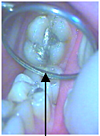

L’inlay est une reconstitution réalisée au laboratoire permettant de remplacer la partie cariée d’une dent vivante en protégeant les parties saines.

Lors de la première séance : la carie est nettoyée puis l’empreinte est réalisée

Deuxième séance : le pansement provisoire est enlevé, la dent est désinfectée puis l’inlay est collé